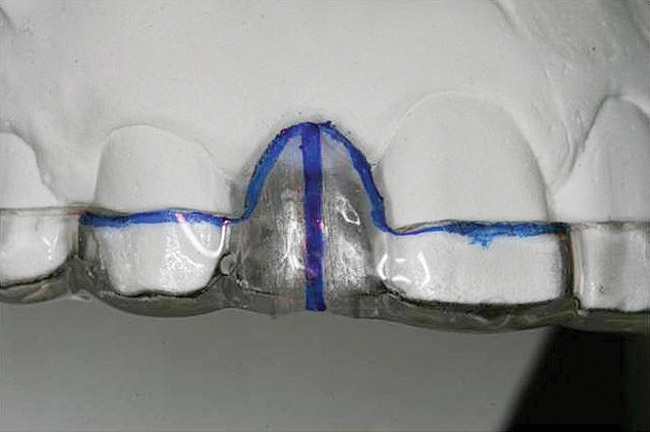

Figure 21   Gingival zenith planning: The location of the gingival zenith for this missing lateral incisor is not fully evident during initial clinical evaluation (Fig 21). Subsequent diagnostic waxing reveals the position of the planned gingival zenith (Fig 22). A thermoplastic template captures the position of the zenith and enables transferring this location to the clinical environment (Fig 23 and Fig 24). Final crown contours are defined by soft-tissue form (Fig 25).

Figure 22  Gingival zenith planning: The location of the gingival zenith for this missing lateral incisor is not fully evident during initial clinical evaluation (Fig 21). Subsequent diagnostic waxing reveals the position of the planned gingival zenith (Fig 22). A thermoplastic template captures the position of the zenith and enables transferring this location to the clinical environment (Fig 23 and Fig 24). Final crown contours are defined by soft-tissue form (Fig 25).

Figure 22